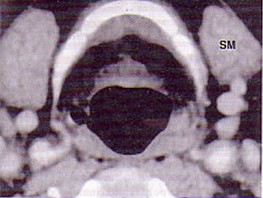

| 男,55岁,声嘶6年,有长期吸烟史。检查:无呼吸困难。喉镜检查:声带慢性充血,可见右侧声带可见菜花样新生物,右侧声带活动固定,喉部CT检查如下图: |

6.诊断首先考虑 ( )![]() ![]() ![]() ![]() |